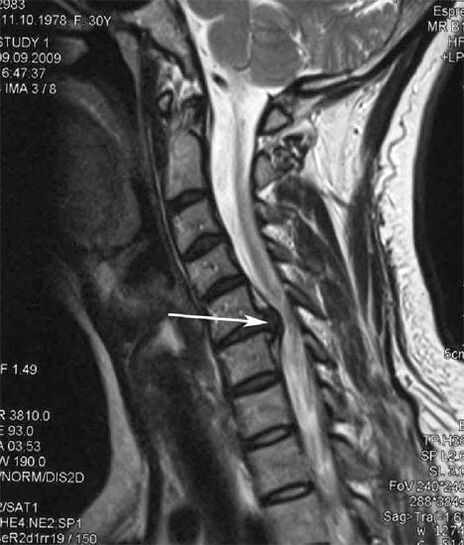

Boshlang'ich bosqichda osteoxondroz MRi-dan foydalanib aniqlandi. Keyinchalik patologiya rentgenografiyasidan foydalanishda tashxis qo'yish mumkin. Bachadon bo'yni rentgenografiya rentgenogrammalarida umurtqalar orasidagi masofa va qirrali bo'g'inlardagi masofa kamayishi va osteofitoz sezilarli bo'ladi.

Ko'p odamlar to'satdan og'ir ishni ko'targandan keyin paydo bo'lgan qattiq og'riq tufayli ularning bo'ynini aylana olmaydilar. Ushbu hodisa churralashtirilgan diskning shakllanishini bildiradi. Orqaga, bo'yin va yuqori oyoq-qo'llardagi og'riqning sababi orqa miyadan paydo bo'lgan asab ildizlaridan birini qisib qo'yadi.